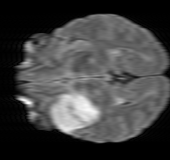

As we observe from the right image in Fig. 2, our BRM, both from MIMO and SISO settings, predicts the performance of dedicated models with a high correlation. We further choose the best three , and perform the last stage of fine-tuning accordingly to (6). A visual evaluation on real data is shown in Fig. 3. For simulated data, please refer to the Supplemental Material section.

Base on the best performing , we perceive that among , , and FLAIR, the results are best when is sampled the most. We suggest that this makes intuitive sense as images provide the best contrast out of the three sequences, which can compensate for the details lost in other images. The same observation can be made on the simulated data, where both and FLAIR show good contrast. When the time setting is changed to non-uniformity, we can see that our search for the best sampling strategy reflects the change. is sampled more as a result of faster acquisition time, while is still sufficiently sampled.

| Sequence | LR | SISO | MIMO | MIMO tuned | GT |

|---|---|---|---|---|---|

|

(f) 29.74/0.8903

(f) 29.74/0.8903

|

(g) 36.25/0.9734

(g) 36.25/0.9734

|

(h) 36.42/0.9752

(h) 36.42/0.9752

|

(i) 37.70/0.9832

(i) 37.70/0.9832

|

(j) PSNR/SSIM

(j) PSNR/SSIM

|

|

(k) 39.89/0.9311

(k) 39.89/0.9311

|

(l) 43.94/0.9864

(l) 43.94/0.9864

|

(m) 44.74/0.9883

(m) 44.74/0.9883

|

(n) 45.49/0.9894

(n) 45.49/0.9894

|

(o) PSNR/SSIM

(o) PSNR/SSIM

|